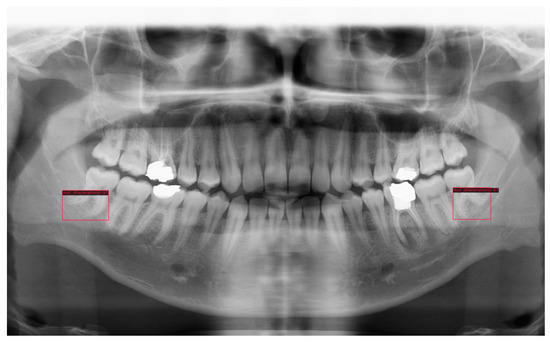

PyTorch and Google CoLab were mainly used to implement deep learning models regarding root dilaceration detection. Figure 2 shows PRs with root dilaceration as an example to show the inputs used for the proposed object detection solution. Before feeding into the deep learning models, data were pre-processed, which included typical operations such as resizing, flipping, normalizing and padding.

Figure 2.

Example PRs with root dilacerations. Red rectangular boxes indicate dilacerated roots that were also used as ground truths. Arrows show dilacerated roots.